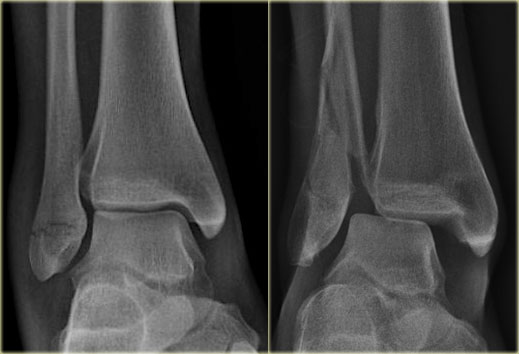

Mortise view

A basic radiographic examination of the injured ankle consists of an AP-view, a Mortise-view and a lateral view.

The Mortise-view is an AP-view taken with a 15-25? endorotation of the foot.

The technologist turns the foot inwards until the lateral malleolus is at the same height as the medial malleolus.

This view visualizes both the lateral and medial joint spaces.

On a true AP-view the talus overlaps a portion of the lateral malleolus, obscuring the lateral aspect of the ankle joint.